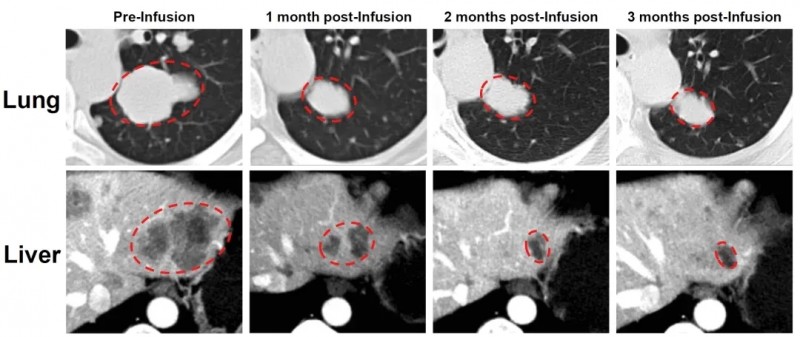

典型案例中,一位卵巢子宫内膜样癌患者入组前经化疗、PARP抑制剂等5种全身治疗,病情仍恶化。在接受GC203TIL细胞治疗后,奇迹正式上演:肝脏和肺部转移灶显著缩小,次月复查靶病灶缩小66%,达部分缓解(PR)标准,为患者重燃生存希望!

▲图源“JUN CELL官网”,版权归原作者所有,如无意中侵犯了知识产权,请联系我们删除

值得关注的是,其中一位晚期肺腺癌案例,该患者确诊为肺腺癌,同时伴随淋巴结、胸膜、骨转移,经GC101治疗后,靶病灶缩小36%,成功达到部分缓解(PR),且治疗24周时仍维持缓解状态。下图展示了该患者在接受GC101 TIL回输治疗前,以及治疗6周、12周、18周、24周的CT影像对比(详见下图)。

▲图源“JUNCELL”,版权归原作者所有,如无意中侵犯了知识产权,请联系我们删除